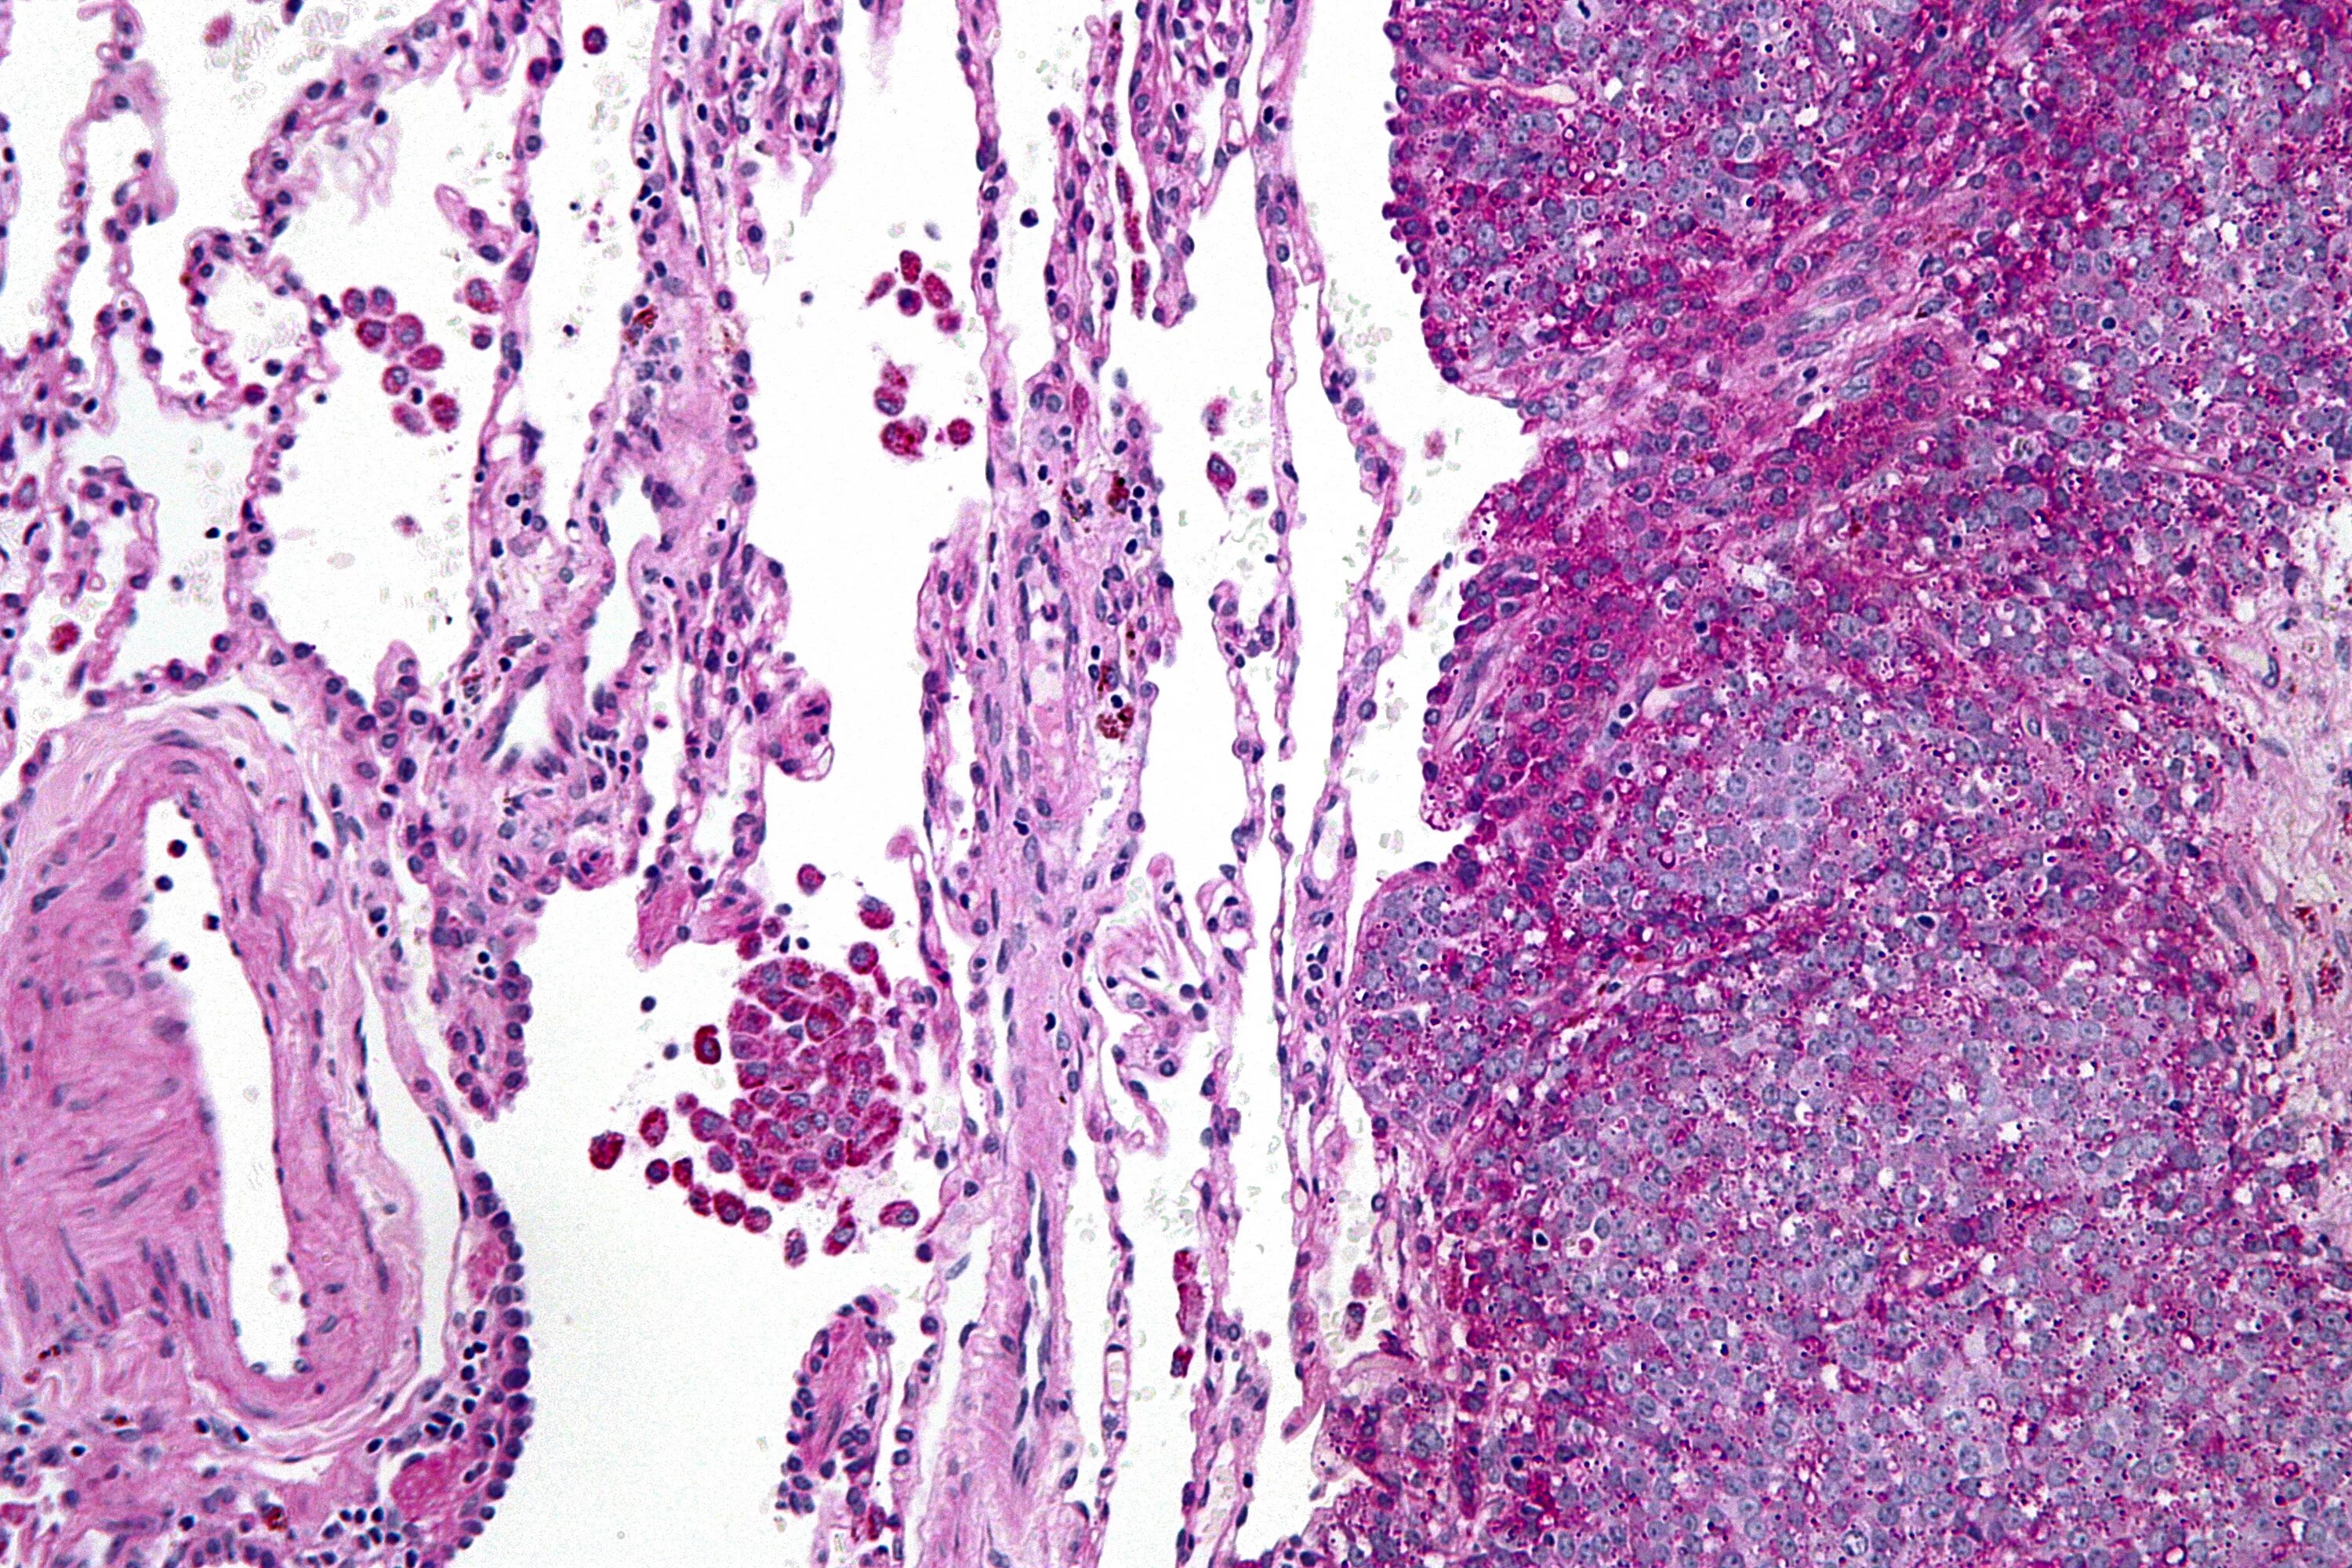

Синовиомы